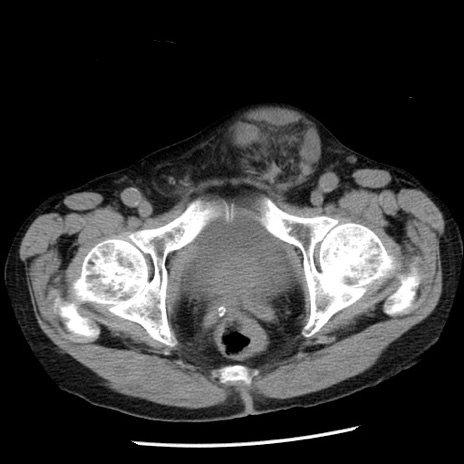

冠状断像

【症例】80歳代男性

【主訴】嘔吐

【現病歴】昨晩2回嘔吐あり、今朝になっても嘔吐あり。来院。

【既往歴】胃潰瘍

【身体所見】意識清明、BT 37.6℃、BP 166/95mmHg、HR 100bpm、SpO2 97%、腹部:平坦・軟、腸蠕動音聴取良好、圧痛なし。

【データ】WBC 21900、CRP 1.46